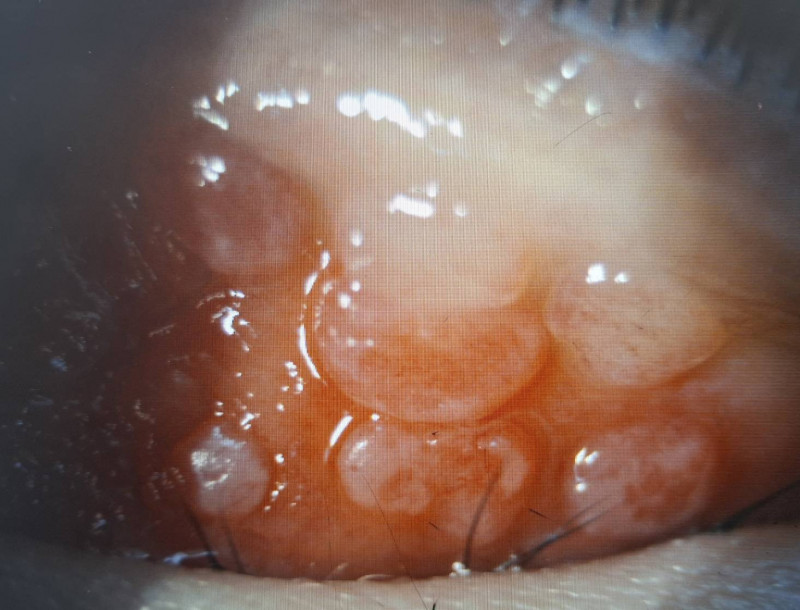

小二男童因長期眼睛癢揉眼,結膜炎導致左上眼瞼出現多顆巨大乳突。(洪啟庭提供)

男童因結膜慢性發炎,使結膜上皮細胞的過度增生,長成大於0.1公分的乳突。(洪啟庭提供)

巨大乳突壓迫不僅造成角膜潰瘍,還出現高度散光而視力模。(洪啟庭提供)